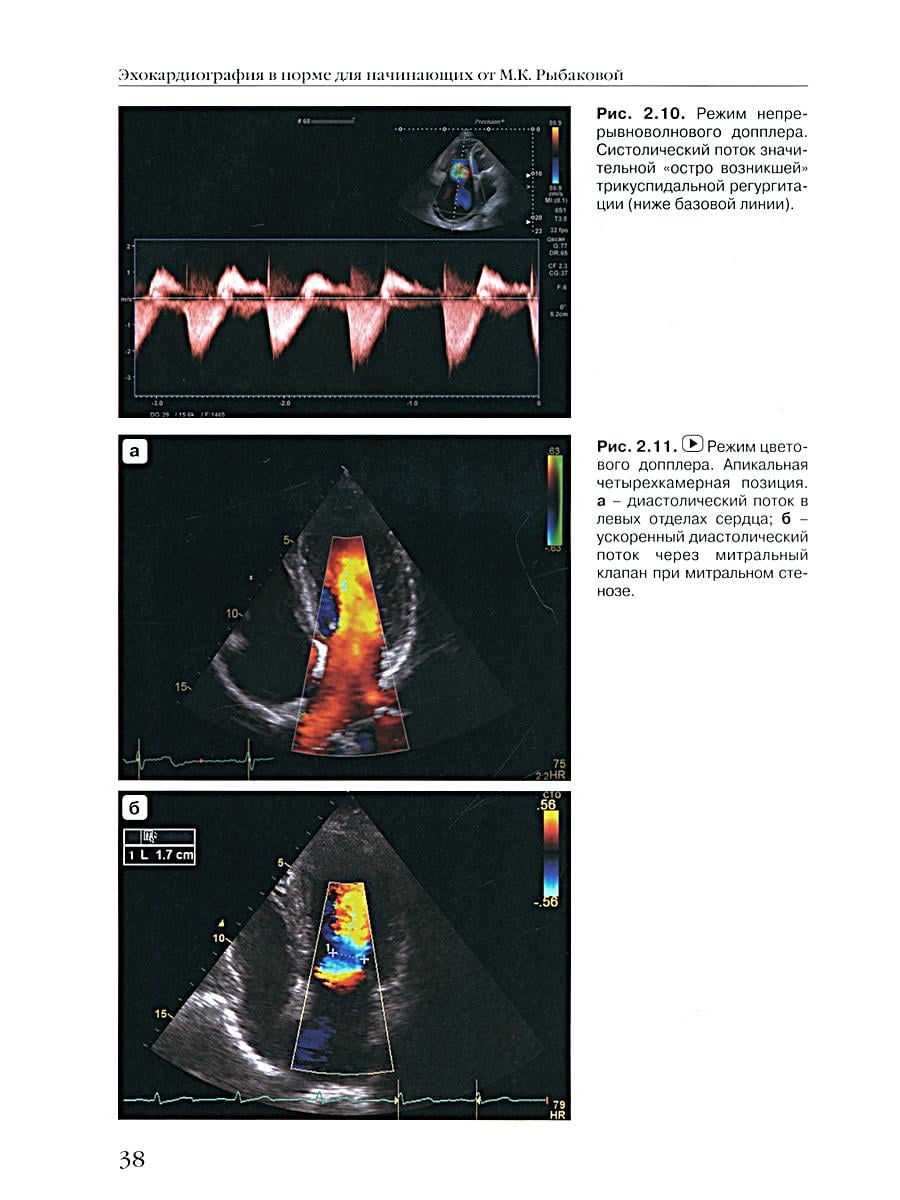

Книга написана сотрудниками кафедры ультразвуковой диагностики Российской медицинской академии непрерывного последипломного образования (база - ГКБ им. С.П. Боткина, Москва). Руководство призвано облегчить начинающим эхокардиографистам погружение в специальность. Книга включает подробное описание всех основных стандартных доступов к сердцу при проведении его ультразвукового исследования в норме, анализ каждой из стандартных эхокардиографических позиций. Особый интерес представляет раздел, содержащий подробное описание нормальной гемодинамики сердца и допплерэхокардиографии в норме. В книге подробно разбираются все основные возможные стандартные измерения как в В-, М-режимах, так и в режиме допплерэхокардиографии. Авторы приводят таблицы нормативов стандартных измерений и расчетов, исходя из новых рекомендаций Европейской ассоциации эхокардиографии. Данное издание содержит большое количество иллюстраций и схем. Книга дополнена видеоматериалами и мастер-классом по нормальному исследованию сердца. Издание предназначено для специалистов эхокардиографии, врачей ультразвуковой и функциональной диагностики, кардиологов и терапевтов.| Издательство | Видар-М |